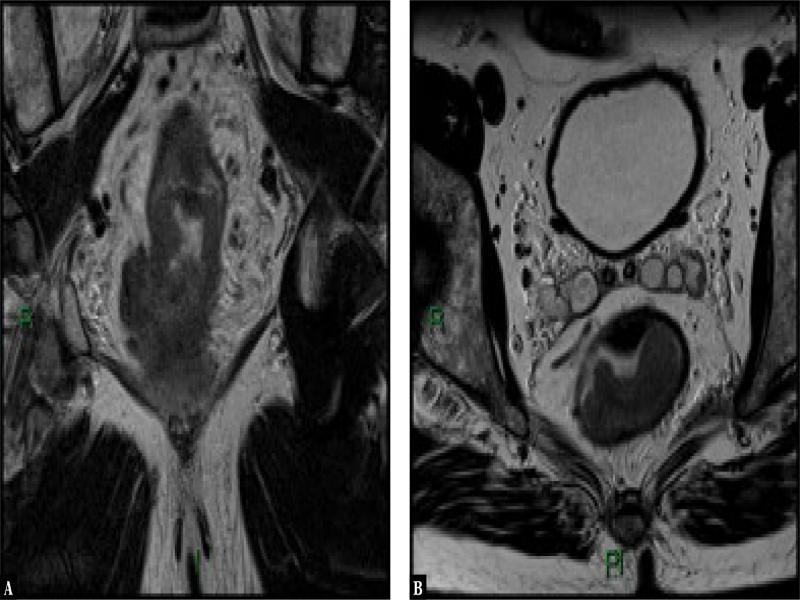

Fig. 3.